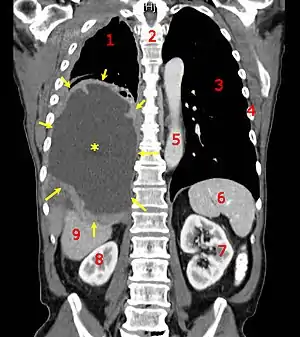

A coronal CT scan showing a malignant mesothelioma

Legend: → tumor ←, ✱ central pleural effusion, 1 & 3 lungs, 2 spine, 4 ribs, 5 aorta, 6 spleen, 7 & 8 kidneys, 9 liver